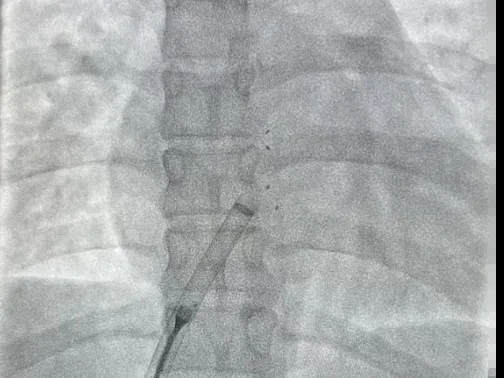

左盘展开

DSA下前推钢缆,后撤鞘管,使左盘面3个Mark点及腰部Mark点推送至鞘管外

牵拉成型线使左盘面成型,并后撤钢缆和鞘管使左盘面贴靠在房间隔